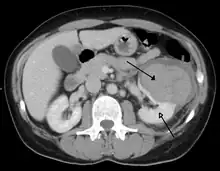

Abdominal trauma resulting in a right kidney contusion (open arrow) and blood surrounding the kidney (closed arrow) as seen on CT

A large hematoma (closed arrow) of the left kidney (open arrow)

The kidneys may also be injured; they are somewhat but not completely protected by the ribs.[6] Kidney lacerations and contusions may also occur.[13] Kidney injury, a common finding in children with blunt abdominal trauma, may be associated with bloody urine.[13] Kidney lacerations may be associated with urinoma or leakage of urine into the abdomen.[4] A shattered kidney is one with multiple lacerations and an associated fragmentation of the kidney tissue.[4]